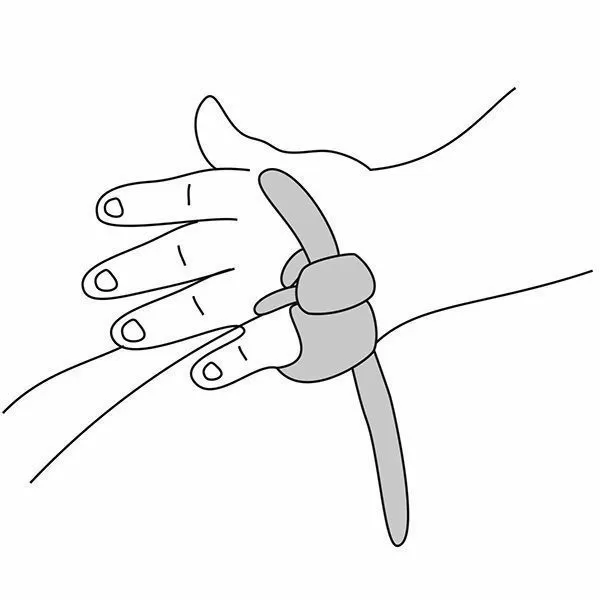

Почему может врать пульсоксиметр?

Причин, по которым пульсоксиметр может проводить измерения неверно, бывает несколько:

- у вас холодные руки. Согрейте их перед измерением;

- вы не до конца поместили палец внутрь прибора или измерению мешает длинный ноготь. Толстый слой гель-лака тоже может быть препятствием;

- вы долго находились в медицинской маске. Снимите ее, подышите глубоко и после этого делайте замер.